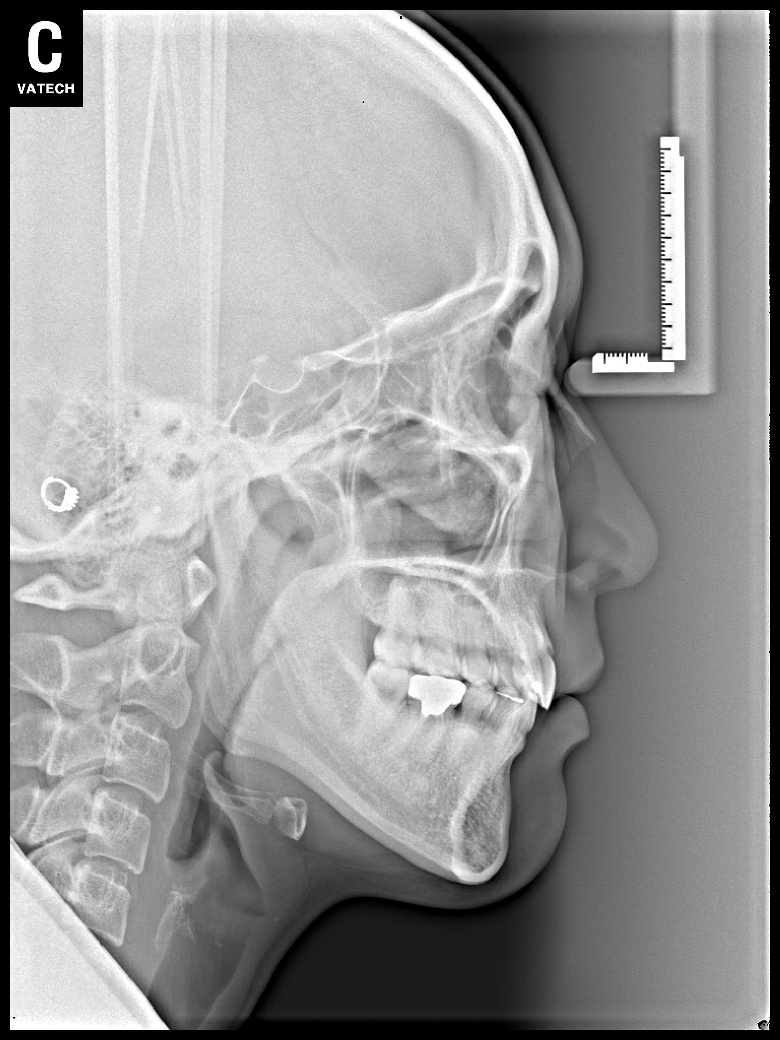

치료 전 사진입니다.